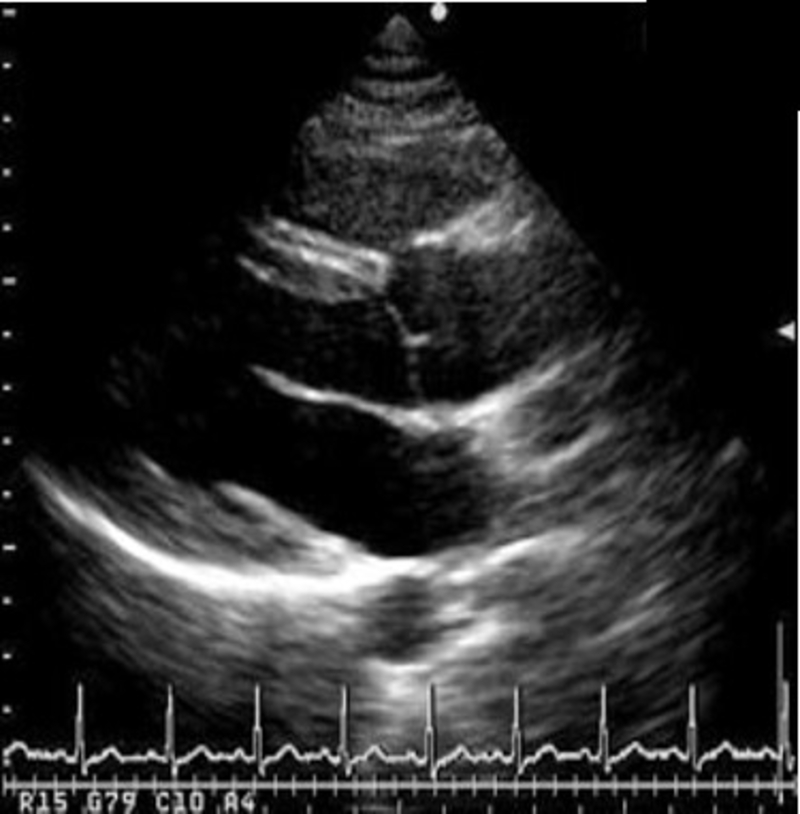

生体検査は、検査を受ける人の身体を直接的に調べる検査です。微弱な電気信号を特殊な機器で増幅し波形として記録します。その代表的な検査が心電図検査や脳波検査です。それ以外にも各種エコー検査(心エコー、乳腺エコー、腹部エコーなど)、肺機能検査として肺活量の測定、AABR(新生児聴力検査)、CAVI(動脈硬化の検査)、呼気検査(ピロリ菌の検査)などをしています。

一般検査 微生物検査 生理検査 超音波検査

尿試験紙法による尿定性検査,尿沈査,便検査,穿刺液検査(髄液・胸水)など 感染症の原因微生物を検査(一般細菌検査,抗酸菌検査,ウィルス検査など) 心電図,負荷心電図(エルゴメーター),24Hホルター心電図,血圧脈波など 心臓,腹部,乳腺,血管など